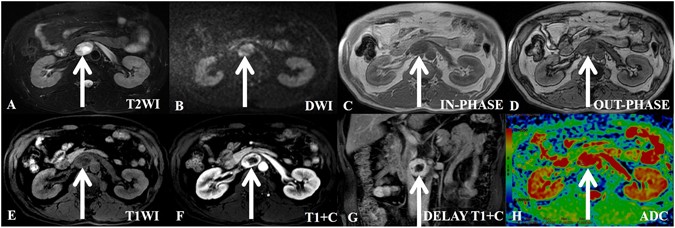

A 47-year-old man with incidentaloma and a histologically proven benign retroperitoneal paraganglioma at the right prevertebral region (among the inferior vena cava, pars horizontalis duodeni and aorta). The transverse and longitudinal diameters of the tumor are 3.92 cm and 3.72 cm, respectively. (A) In axial T2-weighted imaging, the tumor demonstrates high signal intensity and isointensity compared with the gluteal muscles. (B) In axial DWI, the tumor appears with nodular high signal intensity compared with the spleen. (C–E) T1-weighted images (in-phase, out-phase and pre-scanned imaging, respectively); the signal of the tumor is slightly lower than that of the gluteal muscle. (F) In contrast T1WI during the arterial phase, the tumor is clearly enhanced and non-homogeneously ring-shaped. The center exhibits no enhancement of the necrotic area. (G) In coronal T1WI during the delay phase, the tumor shows a continuous and non-homogeneous signal increase. (H) ADC imaging; the mean ADC value of the ROI of the tumor is 0.00180 mm2/s.